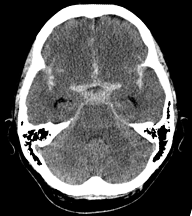

- Gold Standard: Noncontrast Head CT

Hyperdensity in normally dark spaces filled with CSF; namely in the basal cisterns (MOST), Sylvian fissures, lateral ventricles.